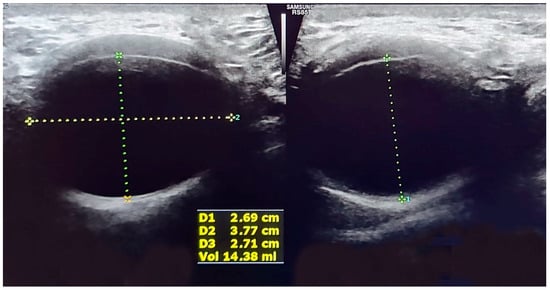

Prospective evaluation of a case series with urodynamic studies performed before and after ATOMS implantation confirmed that direct ventral compression of the bulbar urethra by the silicone cushion significantly increased urethral resistance, which is abnormally low in males with PPI. The bladder outlet obstruction index (BOOI) did not reach a pathological level so as to reflect de novo obstruction [27]. The anteroposterior urethral diameter decreased, and the membranous urethra lengthened with a serial increment of the volume of ATOMS cushion, with narrowing of the urethral lumen in the distal part of the rhabdo-sphincter (Figure 1). Therefore, a double mode of action of ATOMS can be expected to contribute to sphincteric reinforcement. That includes the direct compression of the penile and bulbar urethra and elongation of the membranous urethra.

Figure 1. Lineal perineal ultrasound shows cushion volume filling and ventral compression with narrowing of the urethral lumen and length increase in the longitudinal section (right side image).